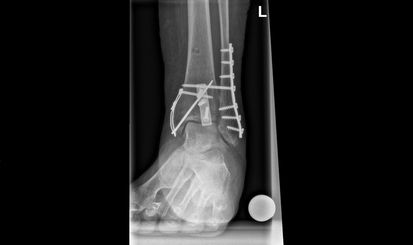

Beim Eingriff werden die Knochenbruchstücke von Altblut gesäubert und wieder in ihre anatomische Form gebracht. Die Fixation erfolgt dann mittels Schrauben und/oder Platten. Sollte die Knöchelgabel aufgrund einer Syndesmosenverletzung instabil sein, ist womöglich eine temporäre Stellschraubenfixation erforderlich. Diese Stellschraube wird 8 Wochen später ambulant wieder entfernt. Die anderen Schrauben werden nur entnommen, falls sie stören – meistens nach einem Jahr oder etwas früher.

Bild: Universitätsklinik Balgrist